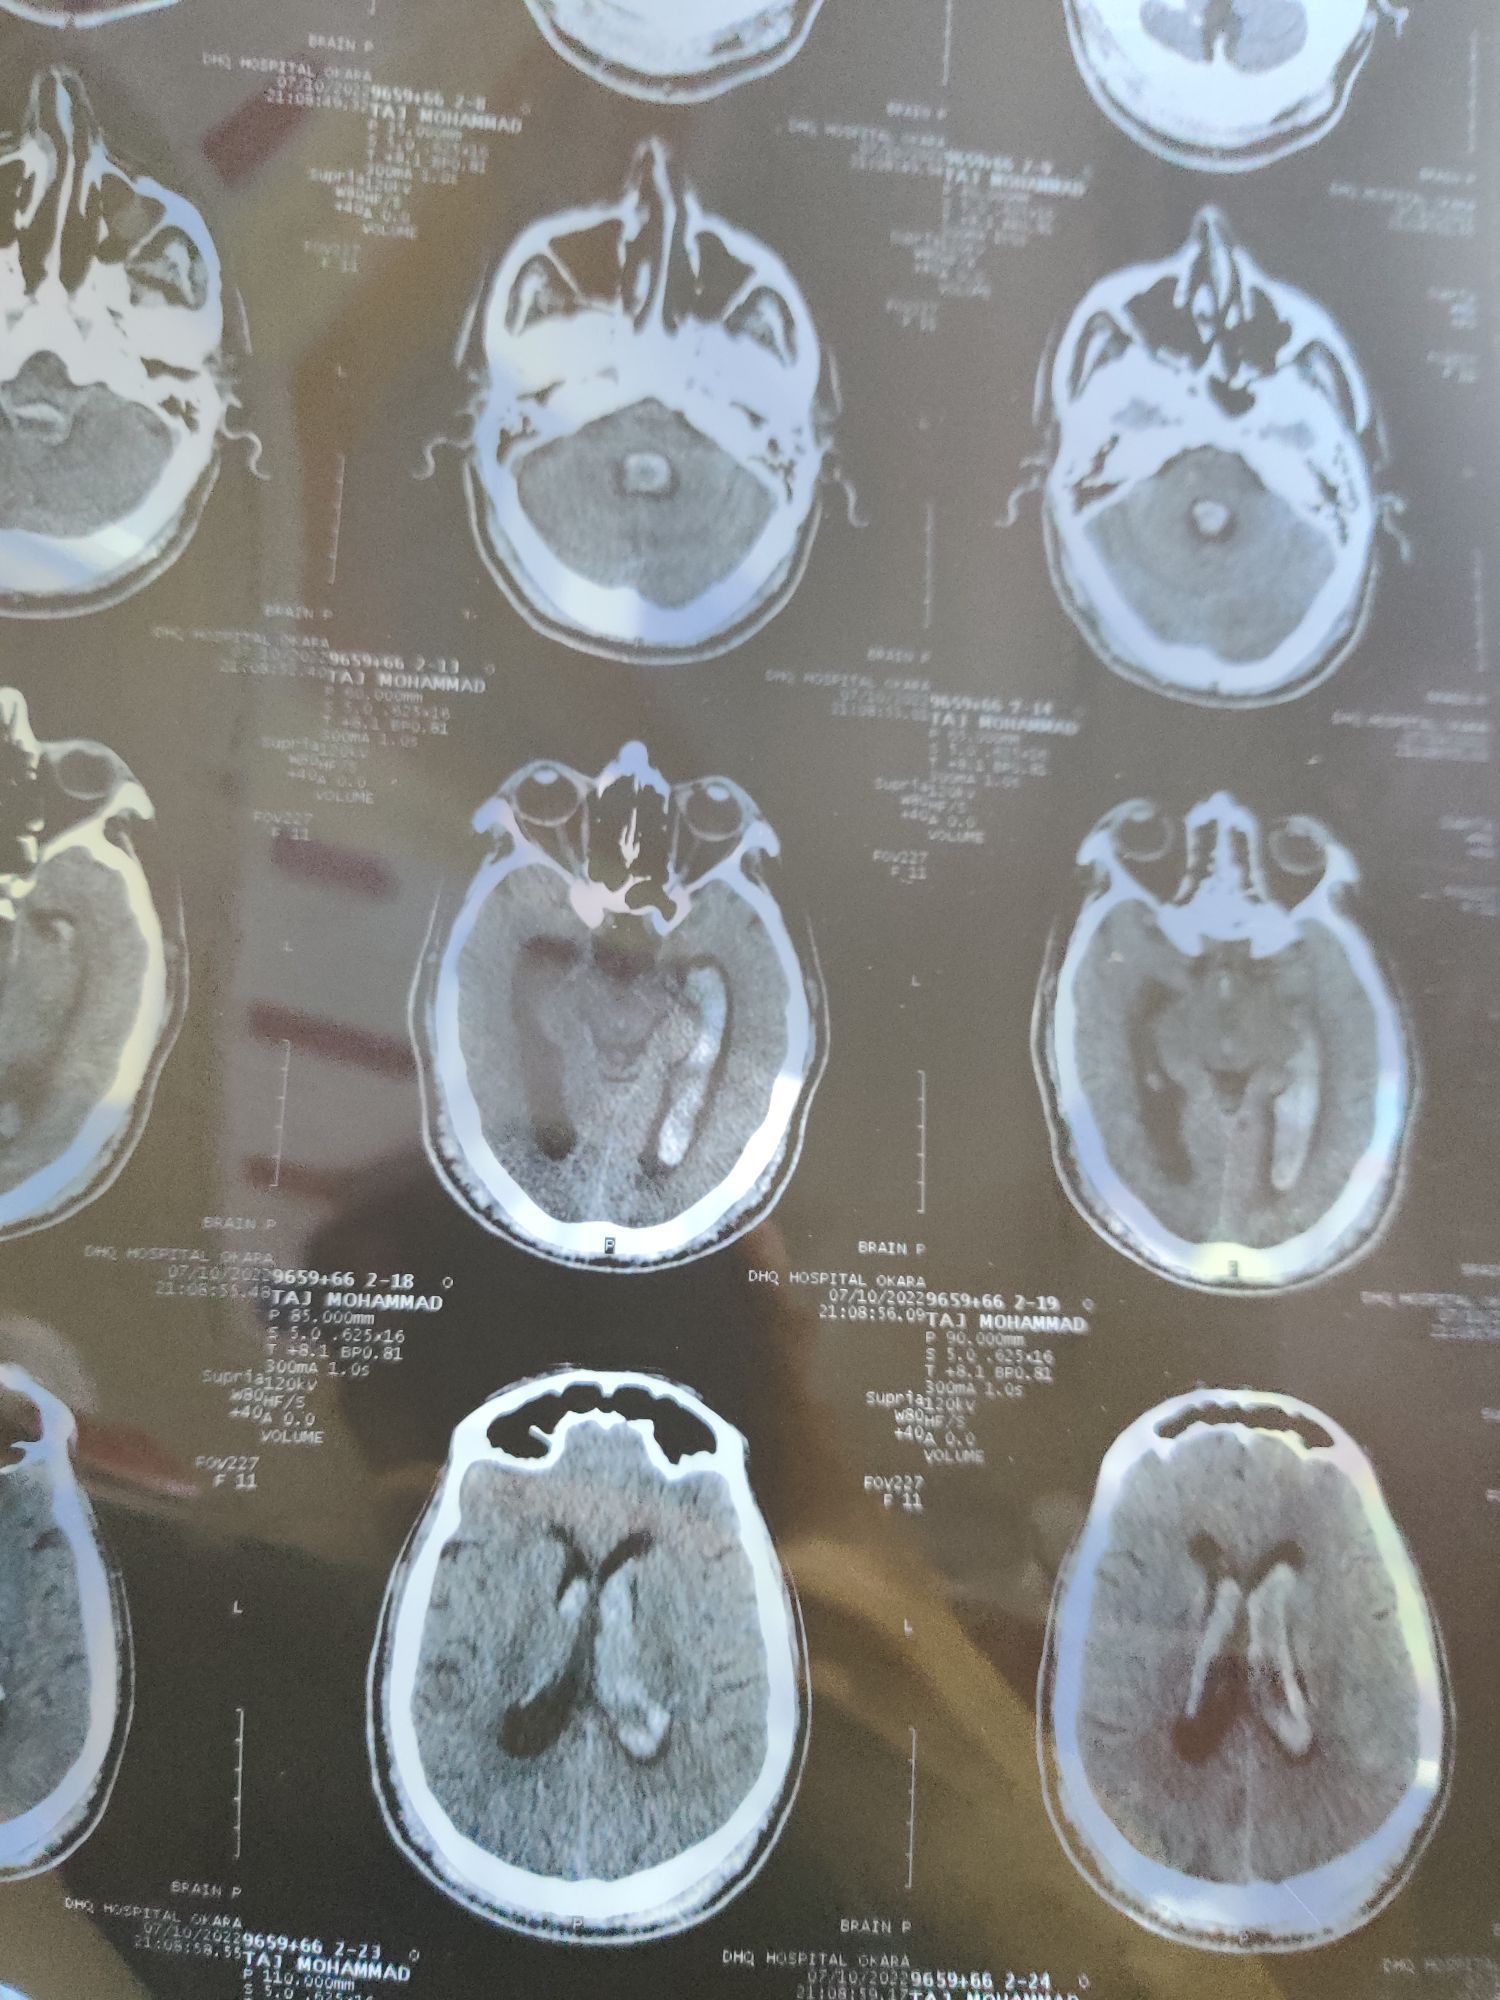

Hemorrhagic CVA extending in both ventricles

Emergency

Cva

Htn